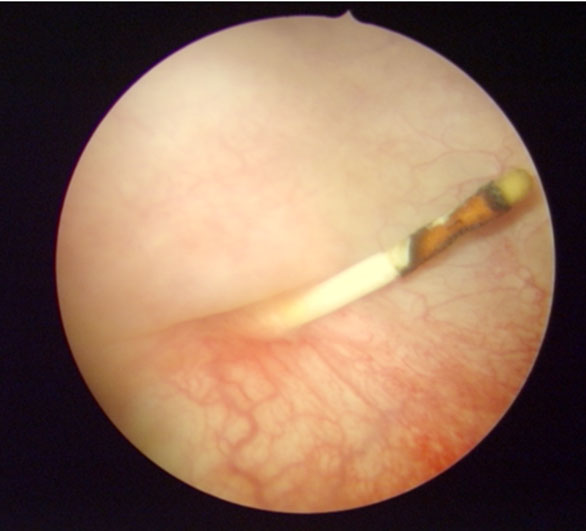

Figure 4: Endoscopic image reveals the IUD through the posterior wall of the bladder.

With the patient under anesthesia, we performed a transurethral resection to remove the IUD (Figure 4). In standard treatment, a minimally invasive approach should be chosen [8]. A more invasive approach, such as a cystotomy, may be required if large stones are present or in the case of associated fistula formations [9].